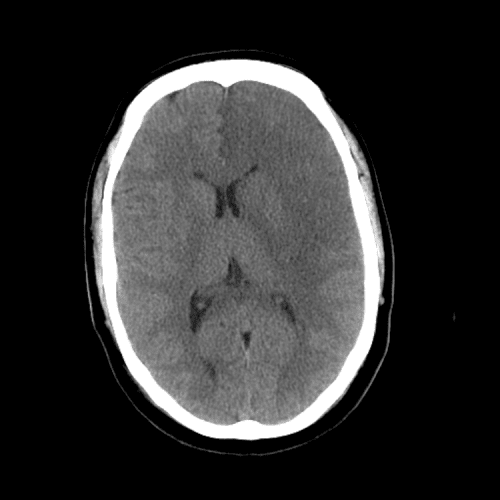

ACA and MCA territory infarct

PCA infarct